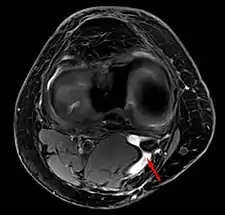

Baker's cyst on MRI, sagittal image